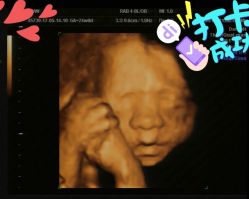

• 杭州贝瑞斯美华妇儿医院·早孕·产检·儿科

• -杭州贝瑞斯美华妇儿医院·早孕·产检·儿科

夜有 上传于 20-05-28 | 报错